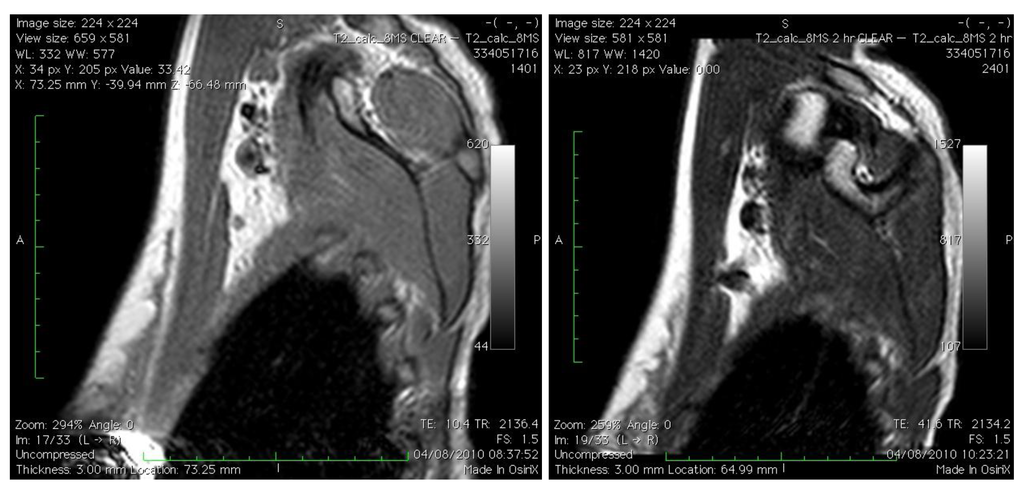

Using an SPIO (Endorem, Guerbet, Paris) injected directly into the breast of women with breast cancer before surgery we have demonstrated the position and morphological appearance of the SLN using MRI scanning (Figure 1) in addition to subsequent intraoperative SLN identification using a hand-held magnetometer (SentiMag, Endomagnetics, UK). Successful identification of the SLN using this technique compared to blue dye and technetium99 was successful in 100% of patients in an initial pilot study [28]. Using SPIO, the SLN is identified with visual inspection of the node (black staining) in addition to localization with a hand-held magnetometer. This technique is a viable, reproducible, non-invasive and non-radioactive method of SLN assessment with successful intraoperative identification.

Figure 1. Left panel: right axilla pre-Endorem injection on MRI scans; right panel: SLN easily identified 120 minutes post-Endorem injection intradermally.